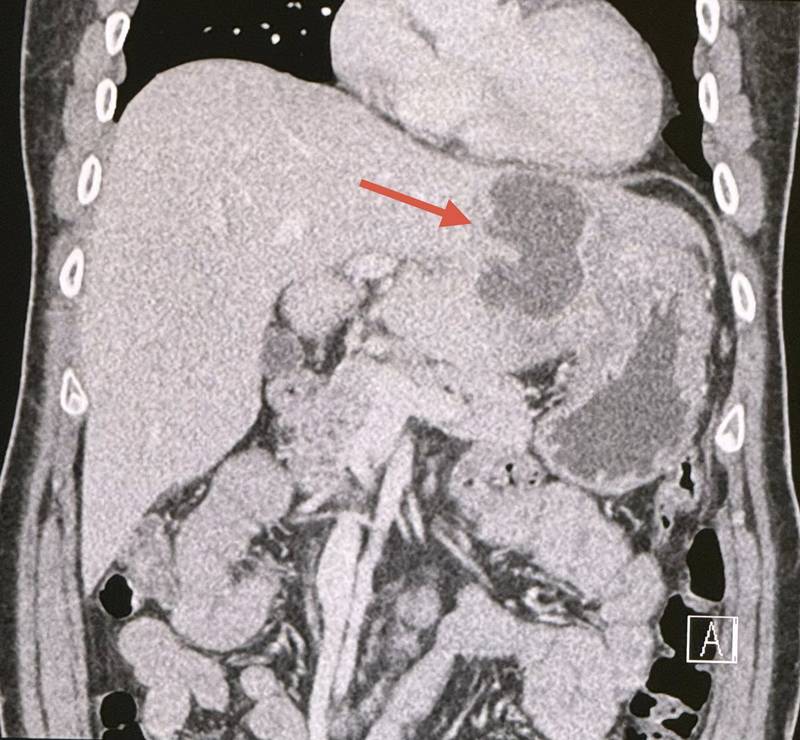

ทำอัลตราซาวด์ช่องท้อง สงสัยฝีในตับข้างซ้าย ขนาด 5.2 × 4 เซนติเมตร ทำคอมพิวเตอร์ช่องท้อง เห็นฝีขนาดใหญ่ในตับด้านซ้าย ขนาด 6.6 × 4.3 เซนติเมตร

วินิจฉัย: ฝีในตับขนาดใหญ่ในคนที่เป็นโรคเบาหวาน